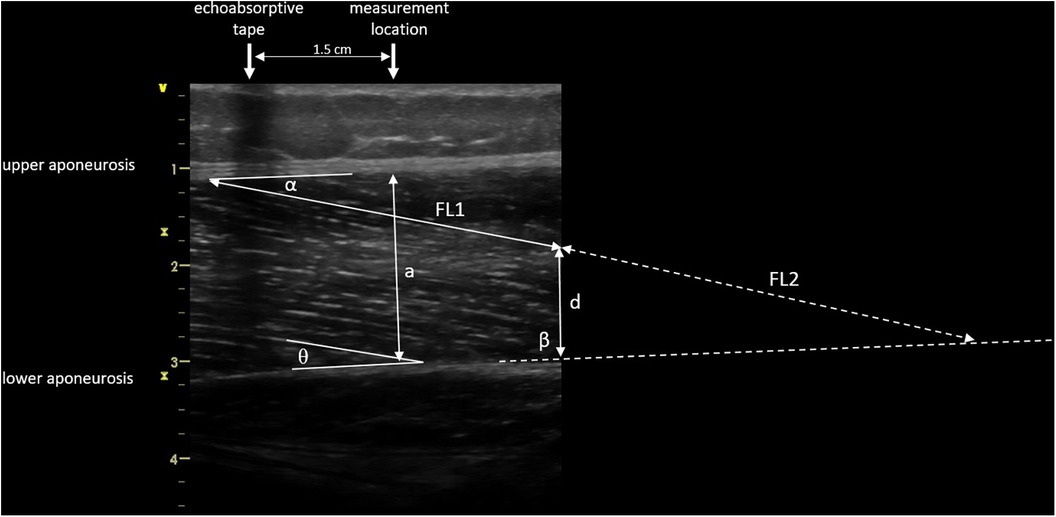

Images were saved and transferred to a computer. Free Java-based ImageJ software (National Institutes of Health, Bethesda, MD, Version:1.53 s) was used to analyze the skeletal muscle architecture (i.e., MT, inferior/superior PA, FL; Figure 5). Due to a calibration image, the Image J software was provided with precise information regarding the specific distance in the captured images that corresponds to 1 cm. After this calibration of the system, distances and angles can be determined by simply clicking on points in the image. Superior PA was measured as the angle between the upper aponeurosis and the fascicle. Inferior PA was measured as the angle between the lower aponeurosis and the fascicle. MT was measured at the predefined position (1.5 cm distal from the echoabsorptive tape) by taking the distance between the upper and lower aponeuroses.

Figure 5. Muscle architecture parameters: muscle thickness 1.5 cm distal from echoabsorptive tape (a), fascicle length (visible length (FL1) + calculated length (FL2) as described by Baudry et al. (21)), superior pennation angle (α), inferior pennation angle (θ), angle between the inferior aponeurosis and the image boarder (β), and height between the inferior aponeurosis and the most distal part of the fascicle in the field of view (d).

In case the fascicle extended the field of view during the ultrasound, according to Baudry et al. (21) FL is calculated from the visible FL (FL1) plus the calculated FL (FL2):

where d is the height between the inferior aponeurosis and the most distal part of the fascicle in the field of view, β is the angle between the inferior aponeurosis and the image border, and θ is the inferior PA.